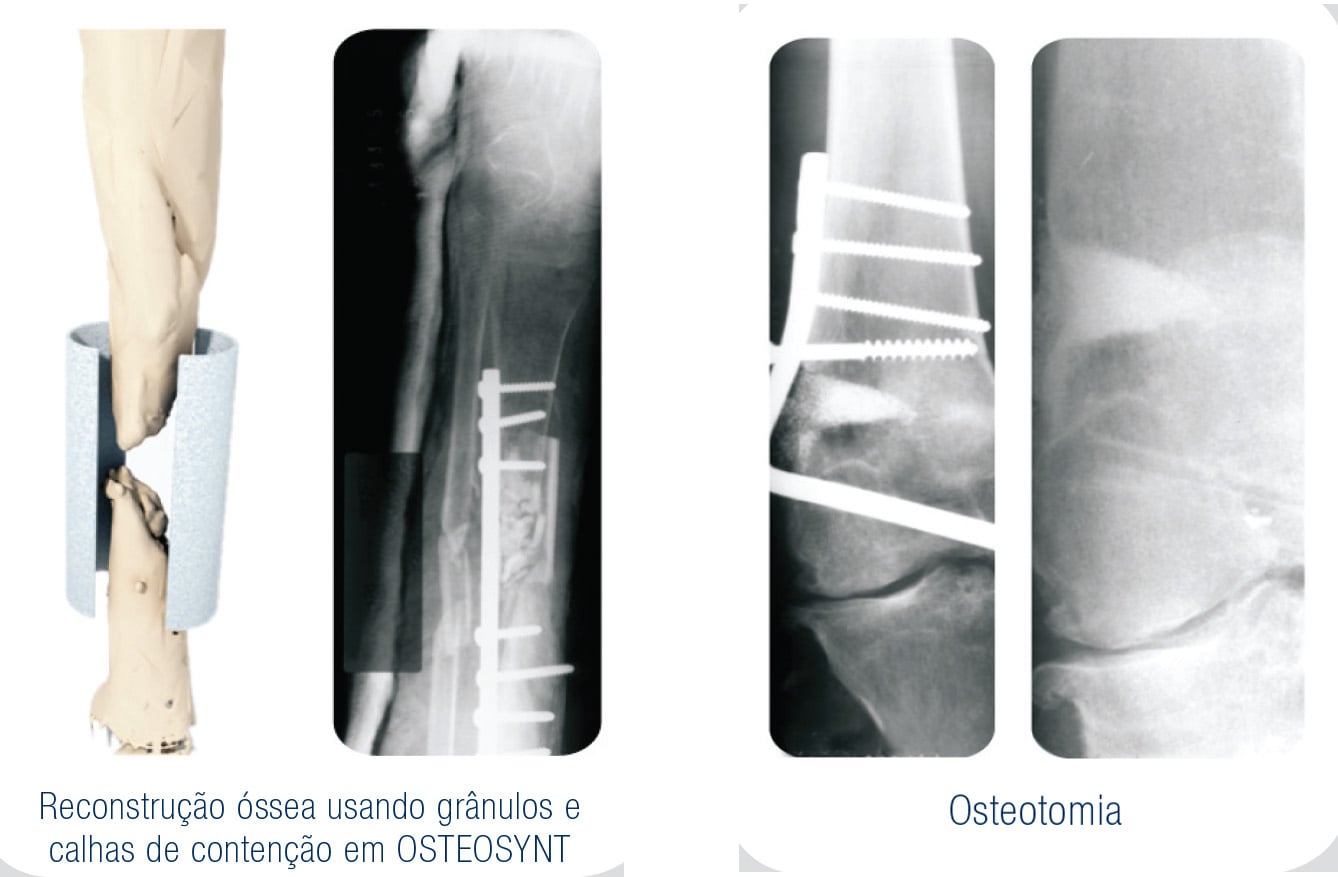

As biossoluções EincoBio para uso na Traumato-Ortopedia criaram novas alternativas com vantagens significativas, principalmente quando substituem materiais de origem orgânica, com a correta indicação naqueles procedimentos.

Com as mais variadas apresentações destes materiais fosfocálcicos, a reconstrução óssea e manutenção de espaços anatômicos, hoje tornam-se uma rotina com a aplicação dessas biossoluções.